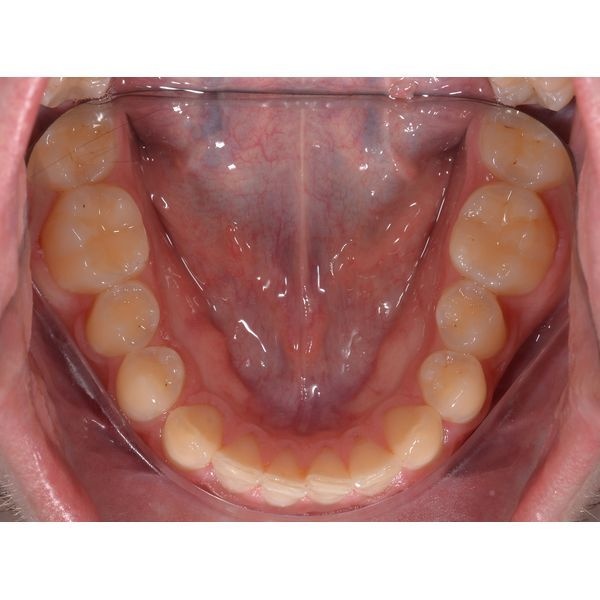

- дефицит места на нижней челюсти;

Также у пациента сохранился зуб мудрости 3.8 (левый нижний). Он рос в сторону зуба 3.7, что повышало риск травматизации этого зуба.

- фотопротокол (серию снимков) полости рта и лица;

- расчёт контрольно-диагностических моделей.